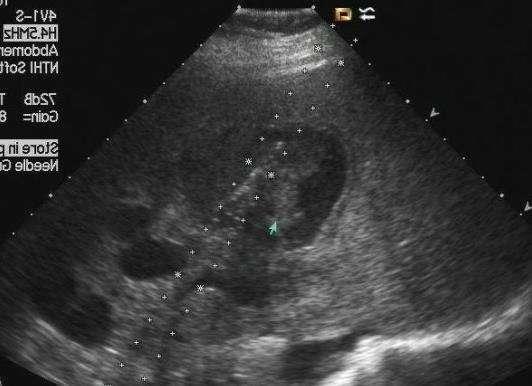

肝内外胆管梗阻 胆管上皮细胞恶性肿瘤可能

案例图:乙肝病史十年 超声显示肝实质回声增粗,增强